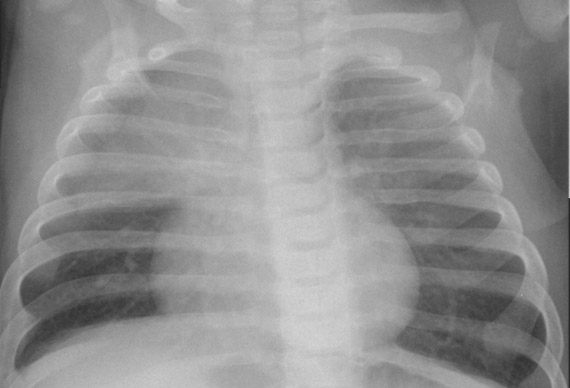

El timo es una glándula mediastínica anterior que forma parte del sistema inmune. En el neonato presenta un tamaño grande en proporción al tórax, y no se suele identificar en radiografías de mayores de 2-3 años. En condiciones normales se presenta en la radiografía como una masa de densidad agua que no comprime la vía aérea ni los grandes vasos, pues es de consistencia blanda y se adapta a las estructuras vecinas.

• Signo de la vela tímica: forma triangular unilateral.

• Signo de la oleada: contorno suavemente festoneado por la impronta de los arcos costales anteriores.

Puede simular una cardiomegalia o una masa mediastínica, a veces puede simular un tumor o una neumonía. Ante dudas razonables, podemos solicitar una ecografía torácica.